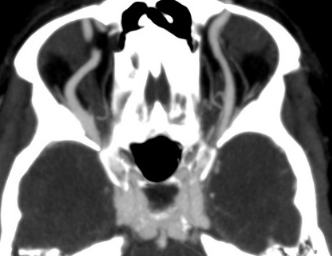

Fistule carotido-caverneuse

- Exophtalmie pulsatile (auscultable)

- Elargissement de la veine ophtalmique supérieure

- Flows voids dans le sinus caverneux

- Opacitifaction précoce du sinus caverneux + veines ophtalmiques sup en artériel